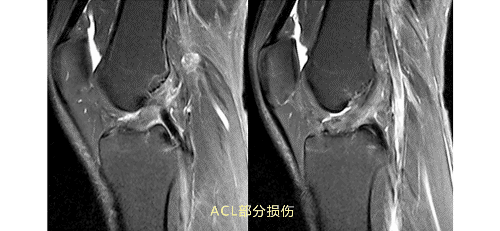

3.gif

ACL损伤的MRI分级——

Grade1:韧带内损伤,无长度改变。

Grade2:韧带内损伤并长度延长。

Grade3:完全性韧带撕裂。

Grade1、2级为韧带的部分损伤,Grade3级为韧带的完全断裂。